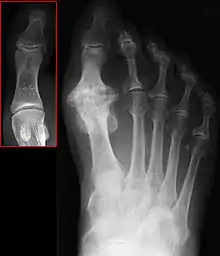

Hallux rigidus or stiff big toe is degenerative arthritis and stiffness due to bone spurs that affects the MTP joint at the base of the hallux (big toe).

| Hallux not labeled but visible at upper left. | |

In 1988, Hattrup and Johnson described the following radiographic classification system:

- Grade I – mild changes with maintained joint space and minimal spurring.

- Grade II – moderate changes with narrowing of joint space, bony proliferation on the metatarsophalangeal head and phalanx and subchondral sclerosis or cyst.

- Grade III – severe changes with significant joint space narrowing, extensive bony proliferation and loose bodies or a dorsal ossicle.[3]